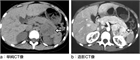

1. 180/120 mmHg以上の著しい高血圧では、予後の向上のために、早急に進行性の心血管系障害の有無を判断し、治療方針を確定すべきである(推奨度1)

1. 高血圧緊急症の症例を診察する際には、臓器障害を示唆する所見(胸痛、背部痛、呼吸困難、神経所見、けいれん、意識状態)の有無に注目する(推奨度1)

1. 血圧は両上肢で測定し左右差を確認する。眼底所見は高血圧緊急症の診断に有用であるため、確認すべきである(推奨度2)